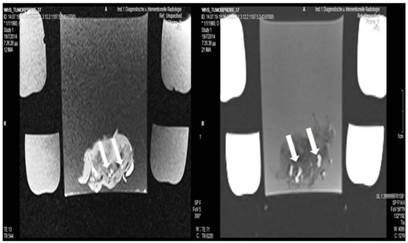

Figure 10

Lipiodol, cisplatin and microwave group; T1 sequence: Heterogeneous appearance with hypodensity sites indicating necrosis. T2 sequence: Heterogeneous appearance with hyperdensity sites indicating necrosis with hemorrhage around the spike wound. White formations are lipiodol molecules entrapped within the tumor tissue (white arrows).

Tumor necrosis and apoptosis were the major purposes of our study. Survival was also recorded. Our records and MRI findings indicate that a major toxicity was observed in the group where cisplatin, lipiodol and microwave were applied. None of the animals survived more than a week. Moreover; hemorrhage apart from necrosis was observed inside the tumors. Survival was the following for the groups: microwave (25days) ≥ cisplatin (22 days) > control (20 days) > lipiodol (16 days)> microwave plus lipiodol (16 days) > cisplatin plus lipiodol (12) > cisplatin plus microwave (12 days) > lipiodol plus cisplatin plus microwave (5 days). (Figure 5-12.)